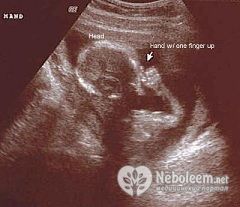

Проведение УЗИ на 16 неделе беременности позволяет определить пол будущего малыша, его наружные половые органы к этому сроку обычно сформированы по мужскому или женскому типу.

Специальной трубочкой врач прослушивает сердцебиения плода. УЗИ на 16 неделе беременности в плановом порядке не выполняют.